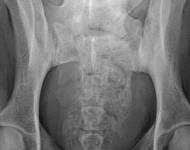

MVDr. Meloun: Lumbosakrální přechodový obratel